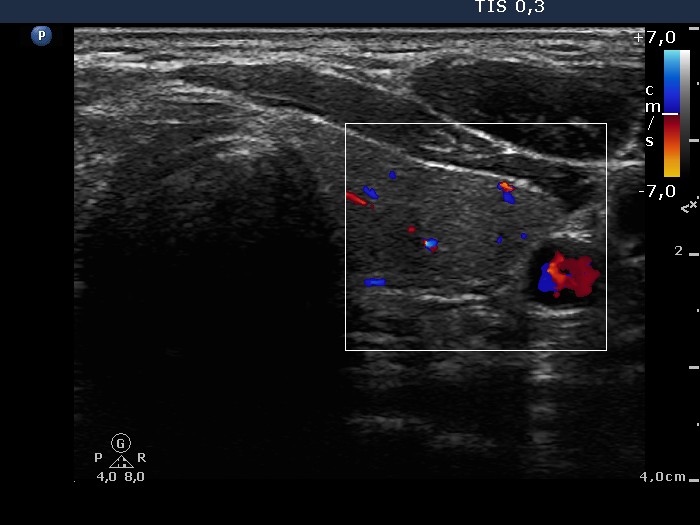

Left lobe, transverse scan, color Doppler mode. The vascularization is not specific.